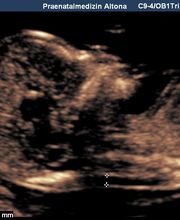

Produktinfos Die Pränatalmedizin ist die vorgeburtliche Medizin (lat. prae- = vor, natus = Geburt), die sich sowohl auf die Schwangere als auch auf den Embryo bzw. den Fötus bezieht. Zur Pränatalmedizin gehören: Pränatale Diagnostik (Erkennen von kindlichen Störungen im Mutterleib) Pränatale Therapie (Behandeln der Mutter und des ungeborenen Kindes) Wir sind ein von der DEGUM und dem GBA zertifiziertes Zentrum, das das gesamte Spektrum des Fachs auf höchstem Niveau anbietet, kurz: Vom ersten Herzschlag bis zur Geburt: Vorgeburtliche Mitbetreuung aus einer Hand In der Pränatalen Diagnostik bieten wir alle Verfahren mit High-End-Geräten der neuesten Generation an: Ersttrimesterschall, Fehlbildungsschall, fetale Echokardiographie, Dopplersonographie, 3D/4D-Ultraschall sowie Punktionen der Fruchthöhle (z.B. Amniozentese, Chorionzottenbiopsie). Auch die cffDNA-Tests sind bei uns bereits fest etabliert. Zum Glück ergeben unsere speziellen Untersuchungen in den meisten Fällen unauffällige Befunde. Wenn es aber leider nicht so sein sollte, lassen wir Sie nicht im Stich. Wir werden Sie in jeder Situation umfassend informieren und begleiten, auch unter Hinzuziehung weiterer ärztlicher Spezialisten. Diese kommen in die Praxis und nehmen an der Ultraschalluntersuchung teil. So kann umfangreich beraten werden, und die spätere Therapie geht Hand in Hand. Zusätzlich legen wir Ihnen besonders in diesen Situationen eine psychosoziale Beratung nahe und vermitteln auf Ihren Wunsch den Kontakt. Unsere Praxis liegt verkehrsgünstig direkt an der A7, Ausfahrt Othmarschen. Ebenso sind wir mit öffentlichen Verkehrsmitteln gut zu erreichen (S1, Metrobus 1). Hierüber besteht auch eine gute Verbindung zur Fernbahn und zum Airport. Wir freuen uns auf Ihren Besuch und wünschen Ihnen eine angenehme Schwangerschaft! Sicherheit für Sie und Ihr Kind Unsere Praxis bietet Ihnen die Kompetenz und Unterstützung die Sie wünschen oder benötigen. Mit modernster Technik besteht heute die Möglichkeit Risiken und Probleme frühzeitig zu erkennen und zu behandeln. Das Team unserer Praxis, bestehend aus Frauenärzten mit der Schwerpunktbezeichnung „Spezielle Geburtshilfe und Perinatalmedizin“ und Humangenetikern, arbeitet auf höchstem Niveau und bietet Diskretion und Vertrauen. Freundlichkeit und Kompetenz sind Teil unseres Verständnisses von Verantwortung. Die passende Begleitung Innerhalb der Pränatalmedizin haben wir uns, neben gängigen 3D-Ultraschall- und Doppler-Ultraschalluntersuchungen, auf die Früherkennung von Fehlbildungen und die Betreuung bei Risikoschwangerschaften spezialisiert. Dazu haben wir uns zum einen auf das erweiterte Ersttrimesterdiagnostik (u.a. mit Nackentranzparenzmessung) spezialisiert sowie gegebenenfalls die weitere Abklärung des Kindes mittels cffDNA-Test, Amniozentese oder Chorionzottenbiopsie. Zum anderen bietet unsere Praxis interdisziplinäre Begleitung bei Zwillings- oder Drillingsgeburten, Fehlbildungen oder Wachstumsverzögerung des Kindes. Unser Praxisteam, die Ärzte für Frauenheilkunde und Geburtshilfe und die Ärzte für Humangenetik, freuen uns auf Sie, Ihr Kleines und Ihre Fragen.